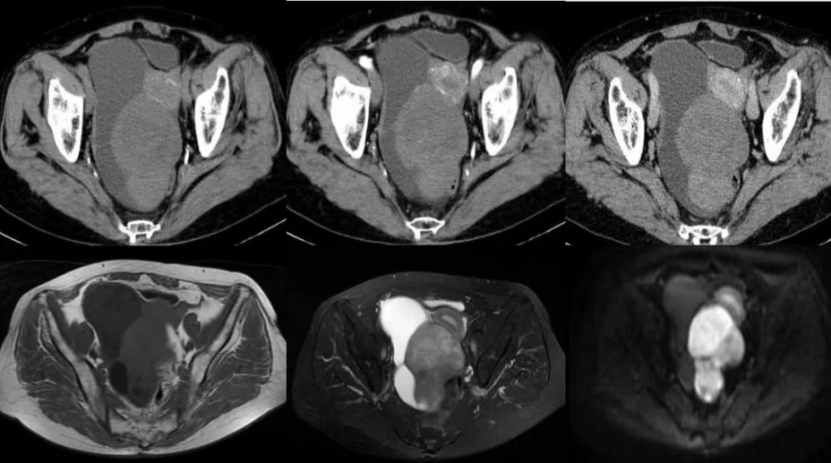

MRI: 盆腔见巨大混杂软组织肿块,实性成分T1WI呈等及稍低信号,T2WI呈稍高及低信号,DWI局部弥散受限呈高信号,测量最小ADC值约0.842×10-3mm2/s,病变内见斑片状T1WI低T2WI高信号,呈“山间云雾状”,肿块边界清楚,大小约163.3mm×129.8mm×127.3mm(前后径×左右径×上下径),增强动脉期内可见细支血管影,动态增强实性成分呈不均匀轻中度渐进性强化,右侧卵巢静脉增粗,子宫、受压狭长、向左前方移位;病变左上方另见一结节状肿块与之紧邻,结节内可见成熟脂肪信号,边界清楚,大小约55.8mm×76.0mm×50.6mm(前后径×左右径×上下径),增强呈环状轻度强化;子宫体积缩小,内膜不厚,信号未见明显异常,增强扫描未见明显异常强化灶;膀胱呈受压改变,膀胱壁不厚,内未见明显充盈缺损;盆腔内见条片状T2WI高信号影;盆腔及双侧腹股沟区未见明显肿大淋巴结。

1.盆腔巨大占位,考虑右侧附件区性索间质肿瘤:卵泡膜纤维瘤,肿块旁考虑畸胎瘤,请结合临床及其他检查;

2.盆腔积液。

右侧卵巢性索间质肿瘤肿瘤:倾向卵泡膜细胞瘤;与病理科老师沟通,较大肿块旁另见一结节,钙化明显,囊内有油脂,倾向畸胎瘤。整合病理结果:右侧卵巢碰撞瘤